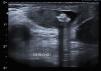

Varón de un mes de vida, asintomático (con ecografías prenatales normales) remitido a consulta de cirugía por identificarse en el control pediátrico una tumoración supratesticular derecha sugestiva de hernia inguinal. Dada la consistencia dura de la misma se realizó una ecografía que evidenció lesiones ecogénicas, heterogéneas y bilaterales con sombra acústica posterior (fig. 1) sugestivas de calcificaciones intraescrotales extratesticulares siendo la mayor supratesticular derecha de 1,2cm y radiografía simple de abdomen que identificaba múltiples lesiones calcificadas intraescrotales sin evidenciarse lesiones intraabdominales (fig. 2).